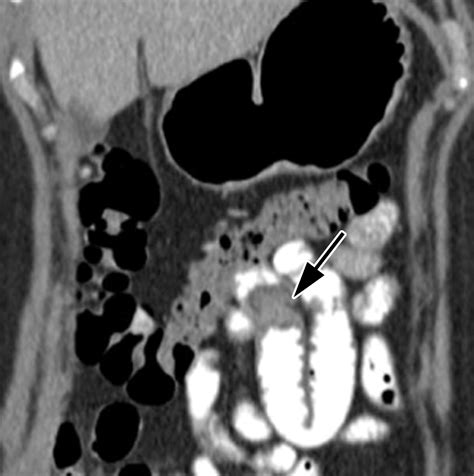

CT or MRI Enterography Cross-sectional imaging that cater detailed views of the enteric paries and smother construction.